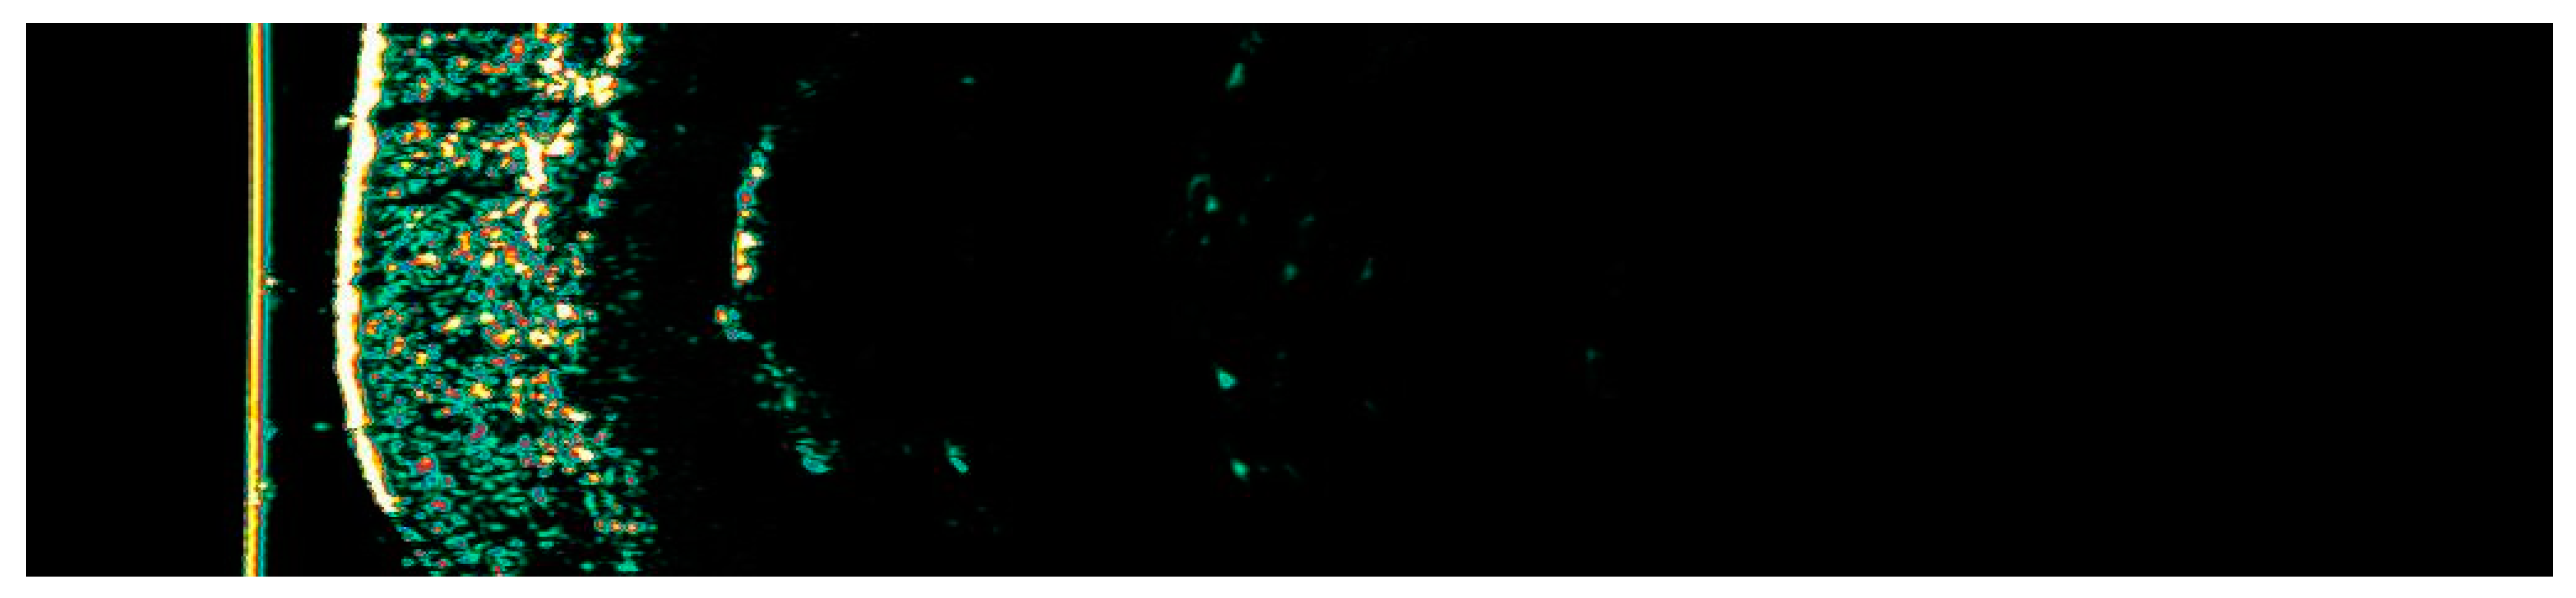

3.1. Clinical and Dermoscopic Involution of HIFU-Treated Basal Cell Carcinoma

| Number of Changes | Vascular Patterns | Pigment Structures | Non-Pigmented Structures | |||||||||||||

|---|---|---|---|---|---|---|---|---|---|---|---|---|---|---|---|---|

| Ambrozing Linear | Short Linear | Loop-like Linear | Bent Linear | Clod-like Linear | Segmentally Arranged | Radially Arranged Linear | Angular Linear | Small Gray-Blue Globules | Large Gray-Blue Globules | White Lines | Small White Structureless Areas | Pink Structureless Areas | White-Yellow Globules | Yellow Globule–Ulceration | Rosettes | |

| 1. | X | X | X | X | X | 3 | ||||||||||

| 2. | X | X | 1 | |||||||||||||

| 3. | X | X | X | |||||||||||||

| 4. | X | X | X | |||||||||||||

| 5. | X | X | X | X | 2 | X | ||||||||||

| 6. | X | X | X | 2 | X | |||||||||||

| 7. | X | X | X | X | 1 | X | ||||||||||

| 8. | X | X | 1 | X | ||||||||||||

| 9. | X | X | X | X | X | |||||||||||

| 10. | X | X | X | X | X | 1 | ||||||||||

| 11. | X | X | X | 2 | X | |||||||||||

| 12. | X | X | X | X | X | 2 | X | |||||||||

| 13. | X | X | X | 2 | X | X | ||||||||||

| 14. | X | X | X | 3 | ||||||||||||

| 15. | X | X | X | X | X | 2 | ||||||||||